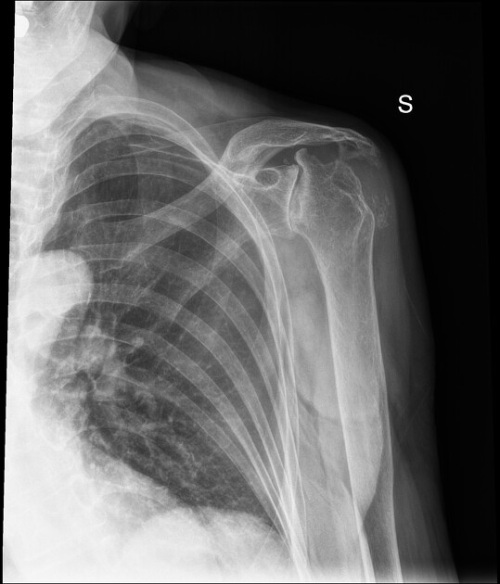

Hình ảnh X-quang khớp via

Hình ảnh X-quang khớp vai của người bệnh viêm khớp dạng thấp bị biến dạng, một phần đầu xương bị tổn thương, ổ chảo bị xói mòn, hẹp khe khớp và xương cánh tay di chuyển về phía đầu. Ảnh: Radiopaedia